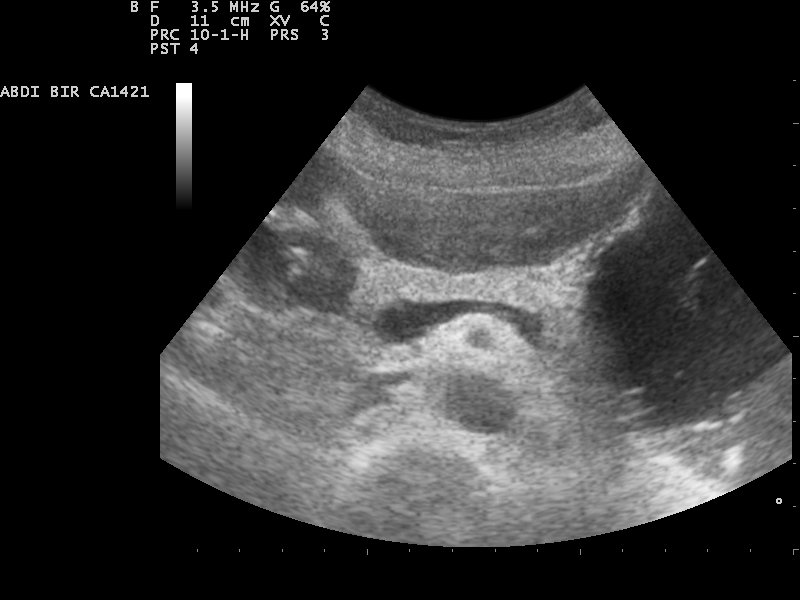

ما هي الكتلة الصدى؟ معنى الكتلة الصدى في الموجات فوق الصوتية الطبية - موقع طبيب أمراض النساء

ما هي الكتلة الصدى؟ بقلم د. بهناز شرف الدين أخصائي أمراض النساء والعقم | 19 أكتوبر، 2017لماذا تسبب منطقة صدى داخل القلب...